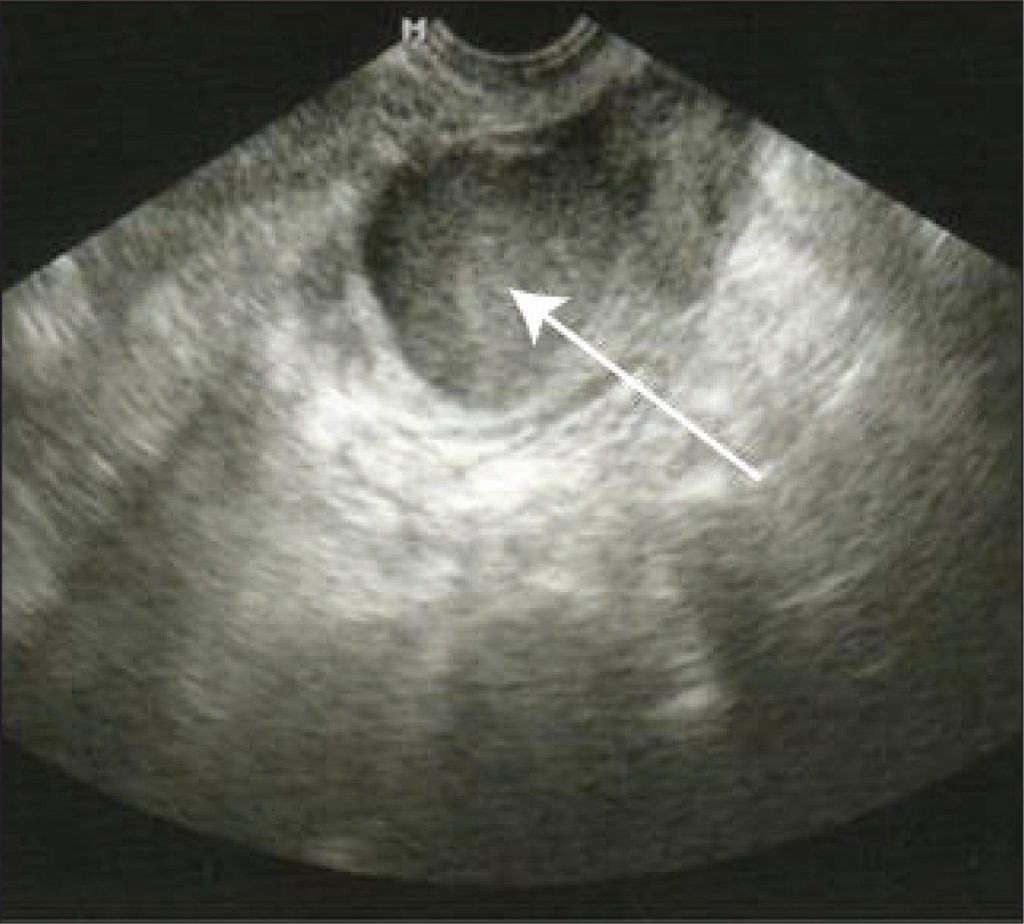

Twenty-one patients with a laparoscopic diagnosis of stage III or IV endometriosis who had an endometrioma larger than 3 cm before ovarian hyperstimulation for in vitro fertilization were included in the study. After using a GnRH agonist analog for at least 20 days, the cysts were punctured using ultrasound guidance and subsequent ethanol sclerotherapy was performed. Then, the patients were stimulated with 100 or 200 U/day of recombinant follicle stimulating hormone, varying the dose according to the patient’s age or history of a previous unilateral oophorectomy.